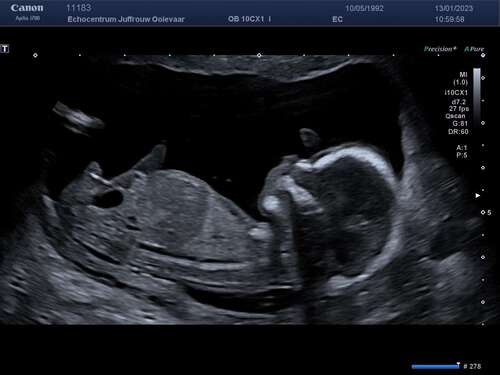

Vandaag dan (eindelijk) de 13 weken echo gehad met 14+3, we zijn ongeveer een half uur bezig geweest om alles te meten omdat de kleine frummel niet stil wilde liggen en telkens met de rug naar ons toe ging liggen. De basis ziet er perfect uit 🥰